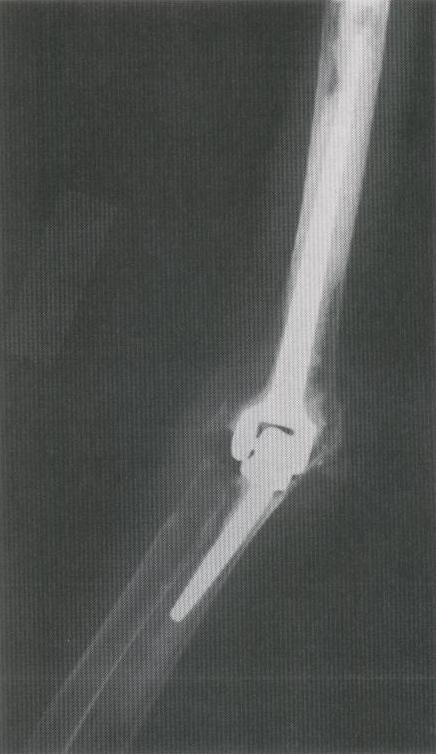

PROTESIS TOTAL PARA CODO

PROTESIS TOTAL PARA RECAMBIO TOTAL DEL CODO

RECAMBIO TOTAL DEL CODO CON PROTESIS